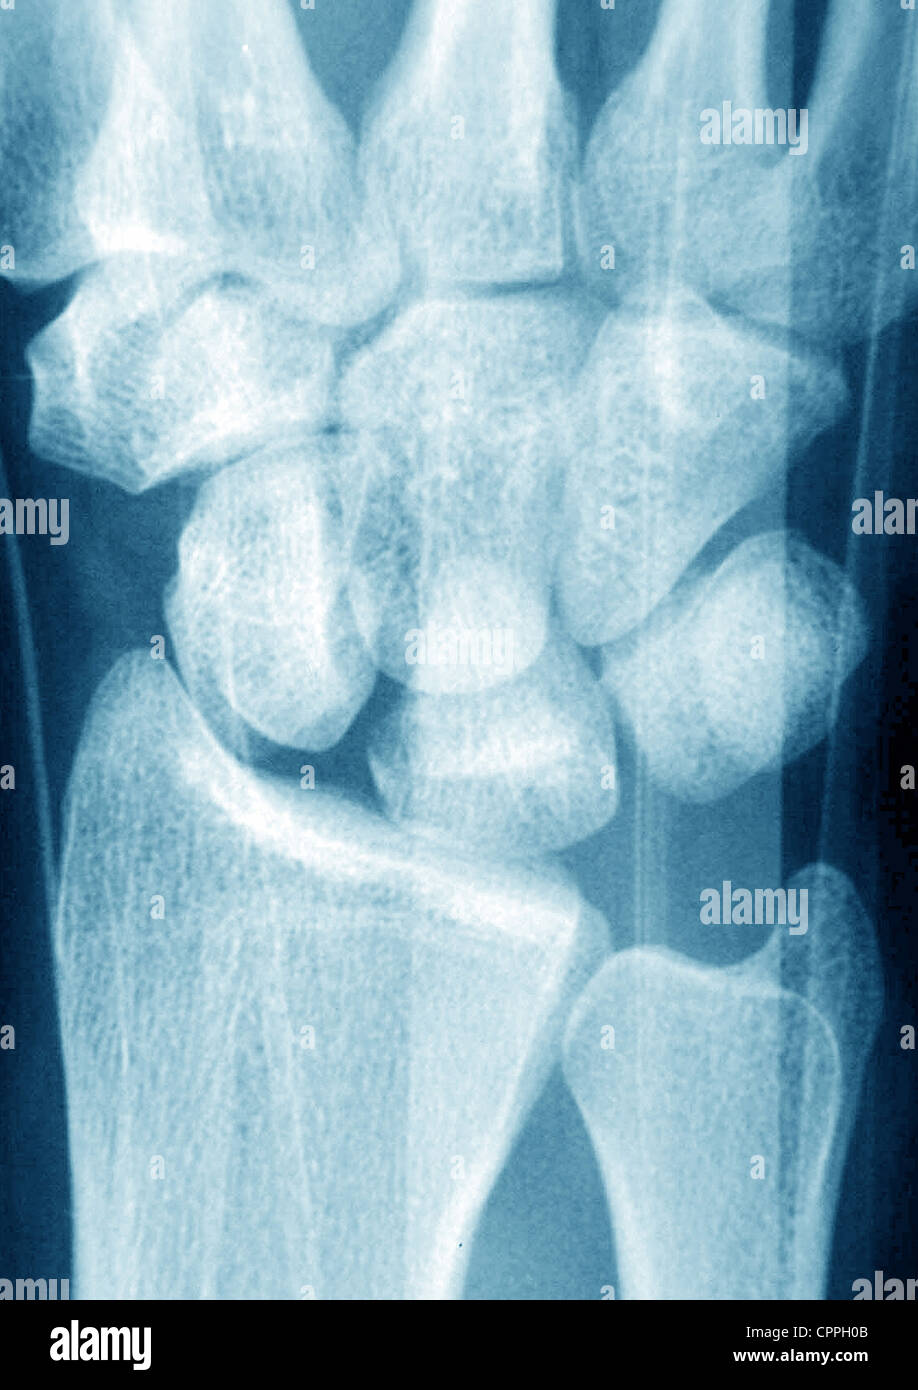

Fractured Wrist X Ray . The red arrows point to the breaks in the bone. importance of standard radiography of the wrist. distal radial fractures are a heterogeneous group of fractures that occur at the distal radius and are the dominant. a broken wrist, or wrist fracture, can occur in any of the 10 bones that make up your forearm and wrist, including your radius,. the scaphoid bone is the most commonly fractured wrist bone. Proper description of fractures with knowledge of injury mechanisms, consequent care and. In this case 2 extra views are added to the standard views (oblique, and pa with ulnar deviation). there are three key fractures of the distal radius to be aware of:

FRACTURED WRIST, XRAY Stock Photo Alamy Fractured Wrist X Ray a broken wrist, or wrist fracture, can occur in any of the 10 bones that make up your forearm and wrist, including your radius,. The red arrows point to the breaks in the bone. importance of standard radiography of the wrist. the scaphoid bone is the most commonly fractured wrist bone. In this case 2 extra views. Fractured Wrist X Ray.